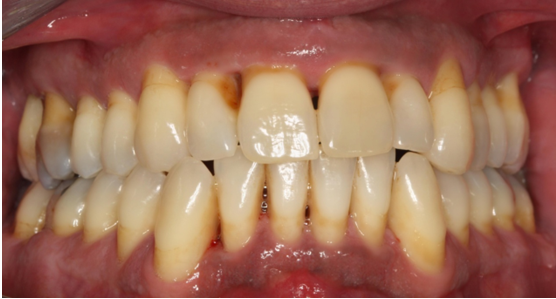

14. Θεραπεία χρόνιας περιοδοντίτιδας σε βαρύ καπνιστή

Ο ασθενής ηλικίας 40 ετών παρουσίαζε περιοδοντική νόσο προχωρημένης βαρύτητας και ήταν βαρύς καπνιστής. Ανέφερε πόνο στα ούλα, αιμορραγία κατά το βούρτσισμα και έντονη κακοσμία. Παράλληλα με τη συντηρητική περιοδοντική θεραπεία, δόθηκε έμφαση στη μείωση του καπνίσματος. Στην κλινική εικόνα κατά την επανεξέταση παρατηρείται απουσία φλεγμονής και ο ασθενής έχει συμμορφωθεί στη στοματική υγιεινή, ενώ έχει μειώσει αισθητά το κάπνισμα.

ΑΡΧΙΚΗ ΚΛΙΝΙΚΗ ΕΙΚΟΝΑ

ΤΕΛΙΚΗ ΚΛΙΝΙΚΗ ΕΙΚΟΝΑ